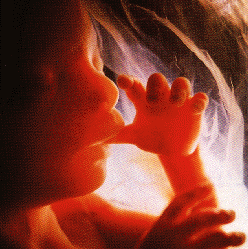

Bebeğiniz amniyotik sıvıdan içmeye başlamıştır. Hıçkırık görülebilir. Boyu yaklaşık 13 santime, kilosu 75 grama çıkmıştır. Gelişmekte olan bebeğin kafası üzerinde lanugo adı verilen ince ve ipeksi tüyler belirmeye başlar. Bu ilkel saçlar doğumda kaybolurlar. Bu dönemde bebeğin cildi oldukça incedir ve deri altında damarlar görülebilir. Bebeğiniz parmağını emmeye başlamıştır.

Bebeğin cilt altı yağ depoları bu gebelik haftasından itibaren hızla artmaya başlar. Bebeğin emme, yutma ve göz kırpma refleksleri de bu gebelik haftalarında ortaya çıkar. Bebeğin kemiklerinde kalsiyum depolama işlemi hızlanır. Parmağını emebilir. Bu haftada bebeğin kalbi günde 30 lt. (1.5 kova dolusu kadar) kan pompalar. Bu hafta sonunda boy 18 cm, ağırlık 150 gr’dır.

Eşiniz elini karnınıza koyduğunda bebeğinizin hareketlerini çok rahat hissedebilir, hatta bu hareketler dışarıdan gözle bile fark edilebilir. Bunun nedeni bebeğin içinde bulunduğu amniyon sıvısının göreceli olarak fazla olmasıdır. Yani bebeğin hareket etmesi için çok geniş bir alan vardır. Bebeğiniz karnınızın içinde takla atabilir, özgürce hareket eder.